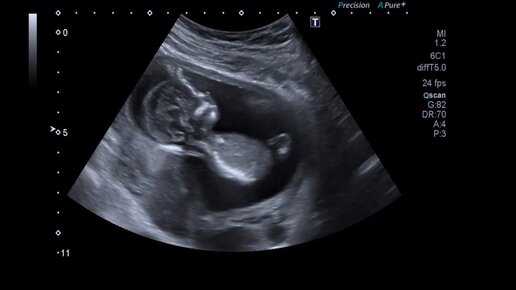

Как младенец в животе пинается. Четкое УЗИ ребенка. Современные медицинские технологий.